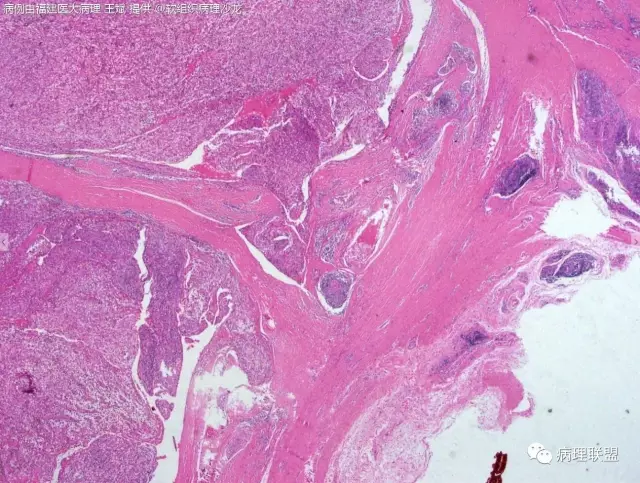

38岁,女性,手部小指背侧皮下肿物,3×2cm(病例由福建医大病理 王斌提供,致谢!)

血管瘤样纤维组织细胞瘤的肿瘤周围有淋巴细胞鞘,结节状分布,有假包膜,出血囊性变的为其主要特点,当然少数病例可以没有出血囊性变却出现粘液变。肿瘤细胞有一定异形性,属于低度恶性或交界性,最好做个FISH,看看有没有EWSR1-CREB1融合基因,刚查了一下,血管瘤样纤维组织细胞瘤还有另一种EWSR1-ATF1融合基因,无论是哪种,用EWSR1分离探针就可以检测